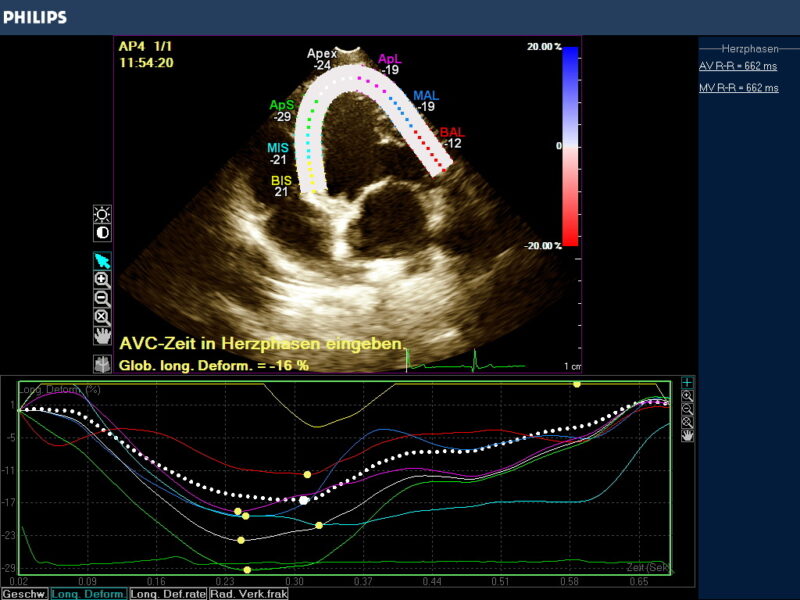

In praxi wird das Myokardium (LV/RV oder Atrien) in 7 Segmente unterteilt, die z.B. für den linken Ventrikel eine Hufeisenform annehmen, die Grenzen dieser enddiastolischen Region Of Interest (ROI) können manuell korrigiert werden über die Software des Geräts. Erfasst wird die endokardiale -, epikardiale Grenze und die myokardiale Mittellinie. Die Akquise der Werte erfolgt automatisch, semiautomatisch oder manuell. Die Einbeziehung des Perikardiums kann zu einer Reduzierung der Strainwerte führen! Die ROI Segmente bekommen Farben und Kürzel zugeordnet (Tabelle 1, Abb.2), die für Myokardsegmente stehen und so können nicht nur globale sondern auch regionale Dysfunktionen erkannt werden.

Der Gerätemonitor gibt die Strainmessergebnis in Form einer Kurve an , deren wellenförmige Line den Farbsegmenten entspricht und die zeitliche Veränderung der Strain beurteilbar macht. Jede ROI hat auch hier ihre definierte Farbe und der Durchschnittswert wird in einer globalen Strain Kurve als weiße Punktlinie angezeigt. Der Anteil der einzelnen Segmente an der GS ist abhängig von ihrer Größe. Das Maximum der globalen Strain GS wird als globale longitudinale Strain definiert (GLS).

Das Ergebnis der GLS wird in negativ -%- Zahlen angegeben. In besonders schwer erkrankten Fällen kann die Zahl positiv werden! Je höher die negative Zahl angegeben wird desto stärker ist die Verformung bzw. Kinesie des Muskels. Darüber hinaus wird nach der Simpson Methode eine Ejektionsfraktion ermittelt , die in EF % angegeben wird (Abb. 3).

Der Kardiologe erhält demnach Aussagen über die regionale Verformungsleistung des Myokards und seine Auswurfleistung. Damit liegen wichtige Werte zur Beurteilung der Inotropie des Herzmuskels vor, die für Diagnostik und Therapie wesentlich sind. In einer praxisinternen Auswertung von 40 asymptomatischen und befundfreien Patienten lag die GLS, ermittelt mit aCMQ Software, zwischen -15 und -25%. Ejektionsfraktionen nach Simpson zwischen 40 und 55%.